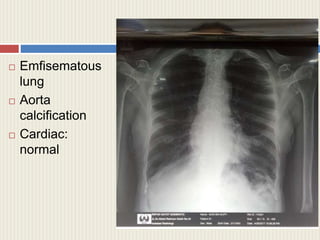

 Emfisematous

lung

 Aorta

calcification

 Cardiac:

normal

Assesment: Rontgen Thorax, ECG, Spirometry test